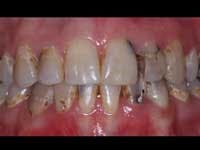

Quality of remaining tooth structure

Assuming that there is a significant amount of coronal tooth structure remaining, the quality of the remaining tooth structure should be considered. Often, remaining tooth structure has discolored areas, slightly demineralized areas, cracks, undermined areas, or other negative characteristics. Removal of tooth structure with these characteristics allows a realistic and necessary appraisal of the amount of viable tooth structure remaining. After removing the affected areas, the same suggestions stated in the previous section on quantity of tooth structure remaining apply. Posts are often indicated.